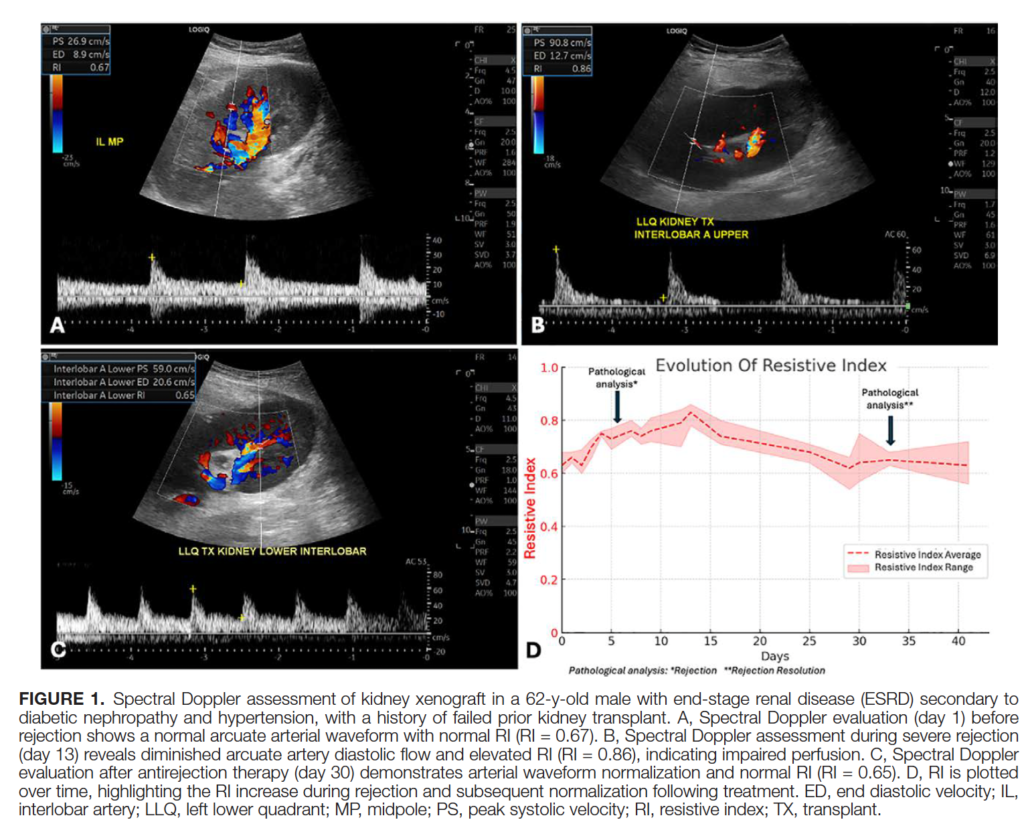

Methods: We report the first application of longitudinal grayscale, color, and spectral Doppler ultrasound in 2 human recipients of genetically engineered porcine kidney xenografts. One recipient additionally underwent serial contrast-enhanced ultrasound to assess parenchymal perfusion. Imaging findings were correlated with serum creatinine trajectories and biopsy-proven rejection.

Results: In both recipients, spectral Doppler abnormalities-including elevation in resistive index-preceded biopsy-confirmed T-cell-mediated rejection. Contrast-enhanced ultrasound in 1 recipient revealed delayed contrast enhancement that paralleled rejection and normalized with treatment. Neither graft demonstrated significant posttransplant growth, with observed changes in graft length remaining within the expected range for Yucatan miniature swine-derived kidneys.

Conclusions: These findings provide the first preliminary ultrasound-based insights into kidney xenograft vascular dynamics and growth patterns, underscoring the potential of ultrasound as an essential tool for noninvasive monitoring of kidney xenotransplants.